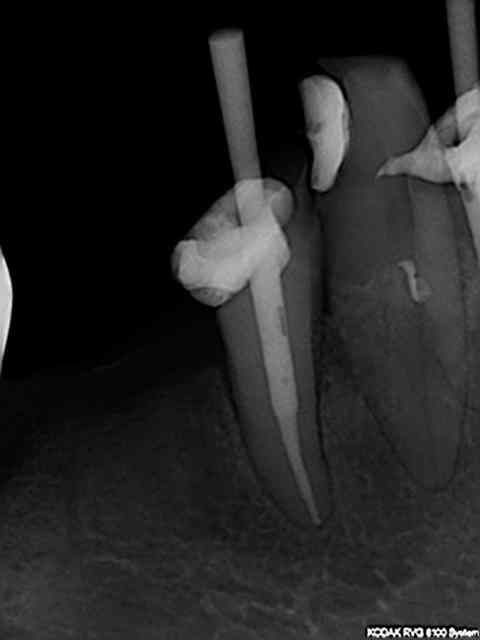

logement canalaire au largo 3, puis machtou vert chauffé au chalumeau.

Radio cône en place avant de le sceller, avec un bon tuck- back et le machtou chauffé au rouge il est rare que le cône reste collé au fouloir. L'avantage de faire la provisoire dans la séance permet de descendre la couronne en plateau et de bien visualiser la chambre pulpaire, particulièrement indiqué dans le cas ci dessus sur des 31 41 d'une personne âgée pulpe rétractée ou à force de la chercher tu trouves .... le desmodonte !))))).